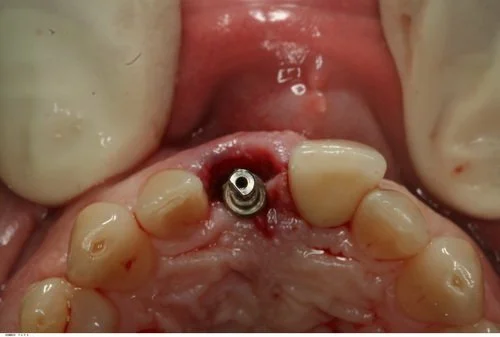

Tooth 21 was removed and due to excellent primary stability being achievable, with good interproximal bone height (Tarnow 1998) a Replace Select implant was placed immediately, with 40+ Ncm of torque being achieved. This allowed for placement of an immediate provisional restoration. The patient’s natural crown was used along with a titanium provisional abutment to construct a pleasing provisional restoration.

The abutment screw was torqued finger tight (~15 Ncm). The access cavity was then restored with cotton pellet and Cavit. The occlusion was adjusted to give no shim stock hold in ICP and no guidance in protrusion or lateral excursion.